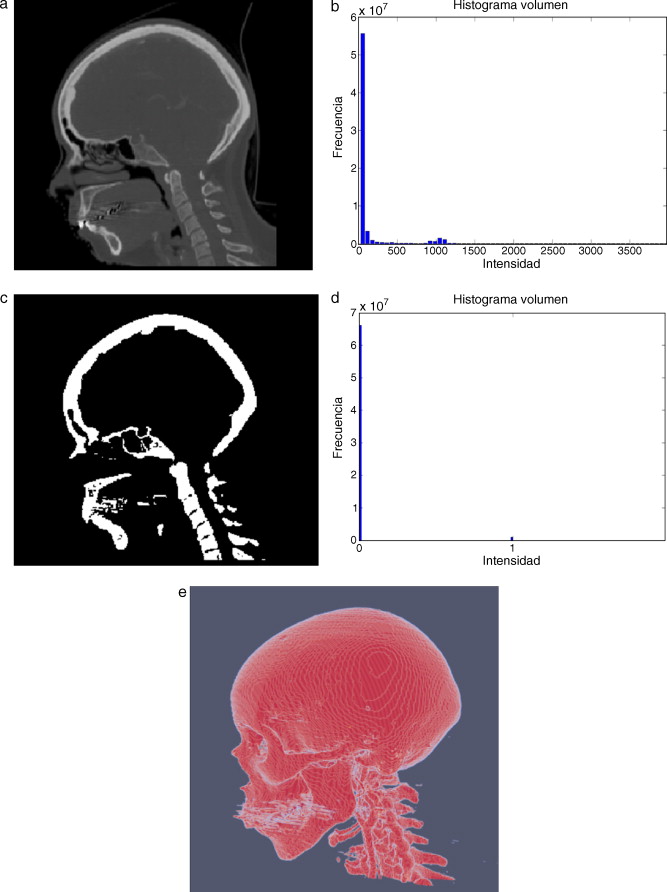

En la figura 9 se presenta el resultado de aplicar la rutina de umbralización global a una imagen tridimensional reconstruida a partir de imágenes de TC cráneo-facial, para segmentar el hueso del cráneo del background y los demás tejidos. En la figura 9 .b se presenta el histograma del volumen total de la figura 9 .a, en el cual se observan varios picos. La aplicación de esta rutina consistió en seleccionar el valor del umbral T igual a 1.235, asignándose el valor de 0 (negro) a aquellos voxels menores a T un umbral de valor 1.235. A los voxels con valores mayores o igual a T se les asignaron el valor 1 (blanco). De esta manera se obtuvo una nueva imagen binaria donde se ha segmentado el hueso cráneo-facial y parte de las vértebras ( fig. 9 .c). El histograma de esta nueva imagen binaria es presentado en la figura 9 .d y la vista 3D del hueso segmentado es presentada en la figura 9 .e.

|

Figura 9. Técnica de umbralización aplicada a imágenes de TC cráneo-facial. (a) Vista original de un corte sagital. (b) Histograma de imagen a. (c) Imagen resultante de umbralizar imagen (a) con un umbral T = 1235. (d) Nuevo histograma de la imagen binaria (c). (e) Vista 3D del volumen del hueso cráneo-facial y parte de las vértebras segmentado con umbralización. |